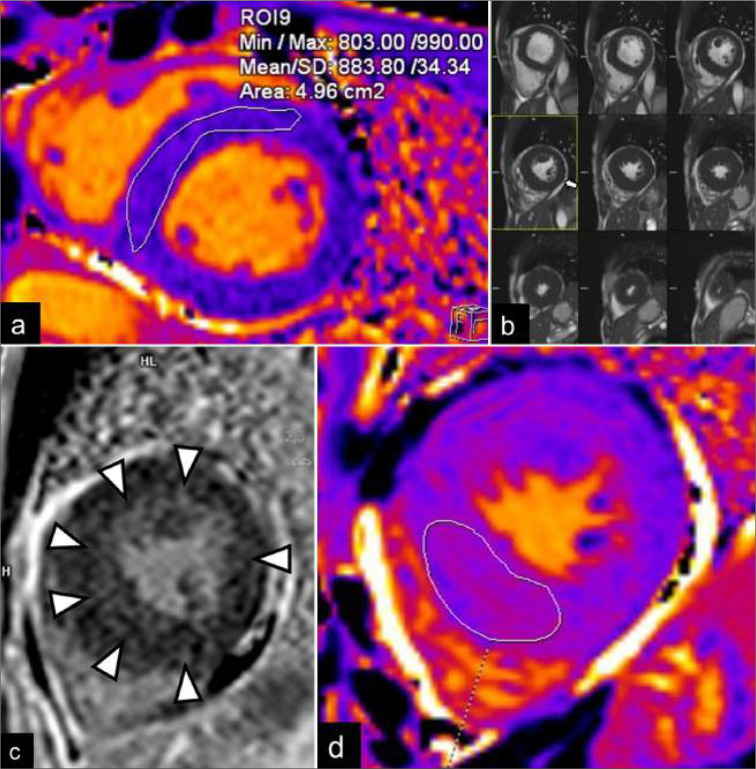

Fabry disease (FD) is a rare X-linked lysosomal storage disorder. Cardiac involvement is frequent in the classic phenotype and late-onset cardiac variant of FD. It is challenging to distinguish FD cardiomyopathy from other forms of unexplained left ventricular hypertrophy, especially in those patients without extracardiac manifestations. Cardiac magnetic resonance imaging is an essential imaging modality for the quantitative and qualitative assessment of FD cardiomyopathy. It helps to monitor disease progress and allows early disease detection in the mild form or subclinical cardiac phenotypes. This review illustrates the characteristic imaging features of FD cardiomyopathy in cardiac MRI, aiming to enhance the awareness of this disease entity among the scope of unexplained cardiomyopathy and promote timely enzyme replacement therapy for patients.